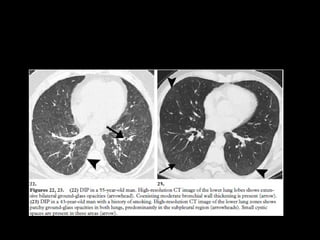

RB-ILD • RB Asintomático,hallazgo • Representan un continuo por la injuria del tabaquismo • Overlap • RB ILD se asocia más a fumadores • DIP: incluye drogas, polvo

CT • Nódulos centrolobularesLS • Vidrio esmerilado • Atrapamiento aéreo • Engrosamiento septal interlobular • DD: neumonitis por hipersensibilidad subaguda, DIP y NSIP

• Biopsia: bronbquiolitisacumulación intraluminal de macrófagos pigmentados

DIP • “alveolar macrophagepneumonia” • Vidrio esmerilado • LI y subpleural • Quistes aéreos, panalziación poco frecuente • DD: RB. NSIP: ausencia de fibrosis, bq x tracción • LBA: macrófagos